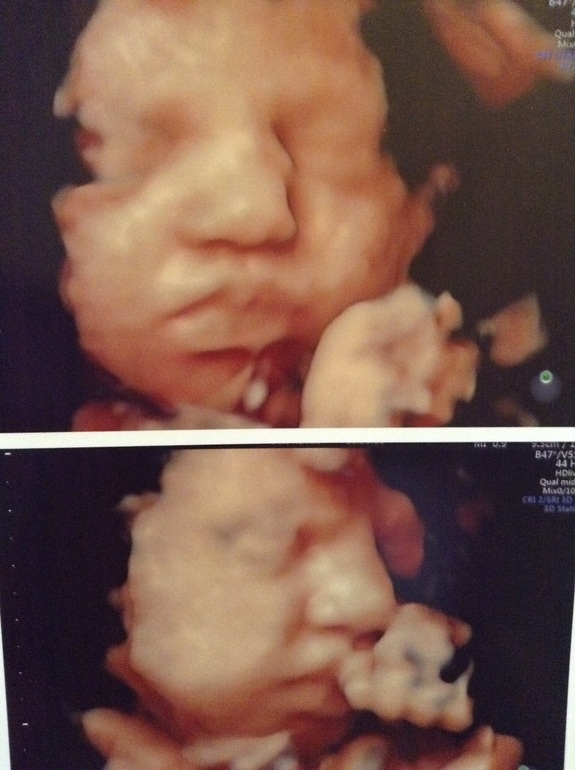

И наши беременные новости и фото моей куколки)))

Всё о нашей беременностиБыла вчера на УЗИ, типо третий скрининг)

Вот такая моя куколка сейчас)) весим мы 1733), по срокам и размерам почти день в день идём) нам сейчас 31,4.., лежим головкой, ротиком вплотную к плаценте, ощущения на экране были, как будто она титю уже сосет))) дядя-доктор сделал нам пару фоток) первое мнение моё было, что доча похожа на сыночка) я с самого начала очень хотела, чтобы она была похожа именно на сыночка) девушка она у меня строгая) даже по мимике лица это видно) обвития ттт нет.., плацента 1 ст зрелости, высоко от зева, доплер отличный))